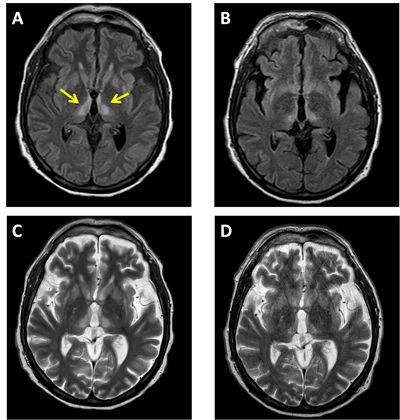

Se inicia retirada de sedación (midazolam + fentanilo), permaneciendo el paciente no reactivo y no perceptivo. A los 20 días de ingreso continua no reactivo y no perceptivo. El TAC cerebral y el electroencefalograma (EEG) fueron normales. Al mes de ingreso se continua sin observar mejoría neurológica por lo que se realiza RMN craneal que informa de lesión talámica bilateral y posible infarto isquémico subagudo talámico bilateral (lesión con alta señal en T2/flair con núcleos mediales del tálamo bilateralmente) (Imagen 1), que podría ser compatible con síndrome de Percheron, como primera opción diagnóstica. Al ser un paciente con antecedentes de enolismo hay que establecer diagnóstico diferencial con encefalopatía de aguda de Wernicke. Se inicia tratamiento con Tiamina a dosis altas.

En la RMN de este paciente se encontró lesión con alta señal en T2/flair con núcleos mediales del tálamo bilateral, compatible con Síndrome de Percheron. En la encefalopatía de Wernicke se pueden detectar lesiones periventriculares y diencefálicas en su fase aguda, sobre todo afectando a áreas simétricas, con incremento de la señal en T2 y descenso en T1. El 100% de pacientes con encefalopatía de Wernicke muestra lesiones bilaterales en los núcleos talámicos dorsomediales y un 30% en el vermis cerebelar superior. Estas áreas presentan un elevado metabolismo y requerimiento por tiamina, lo que las predispondría al daño provocado por su déficit. Se necesita un déficit de 2-3 semanas para deplecionar las reservas corporales, posterior a lo cual se comienza a evidenciar el daño orgánico. La principal diferencia, es que los hallazgos en T2 pueden desaparecer en tan solo las primeras 48 horas tras la administración de tiamina. Nuestro paciente mostró una mejoría neurológica lenta y fue dado de UCI con nivel de consciencia oscilante a los 52 días de ingreso y en la RMN de control, un mes después de la primera, persiste la lesión con alteración de la lesión en T2/flair en los núcleos paramediales del tálamo bilateralmente, pero con disminución del tamaño respecto al control previo, tanto los datos clínicos como de imagen apoyan el diagnóstico de Síndrome de Percheron.